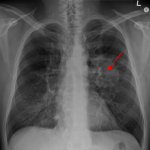

(Cancro-Immagine Credit Public Domain).